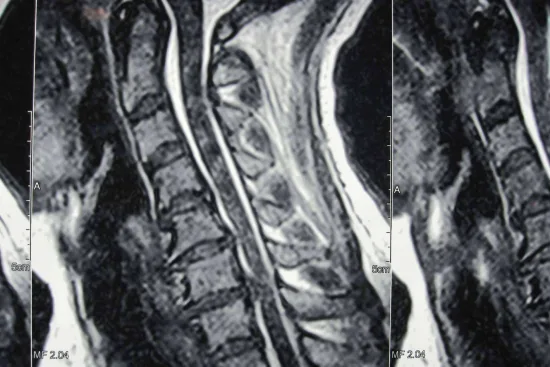

Además de ser un soporte para el tronco, la columna vertebral también es un protector de la médula espinal, así como el punto de unión de las costillas y los músculos de la espalda. Entre cada vértebra de la columna, hay discos cervicales, una especie de amortiguadores naturales para el impacto de las acciones cotidianas, que distribuyen las cargas a las que se expone la columna. Pero, con el paso del tiempo, de manera natural se va degenerando poco a poco, produciendo fisuras que pueden generar diferentes patologías, tales como la hernia discal cervical. Esta se produce cuando uno de los discos intervertebrales degenerados se rompe en algún punto de su circunferencia. Esto causa que su contenido salga y presione un nervio cervical, causando dolor que en los casos avanzados puede llegar a ser muy intenso, limitado el movimiento y afectando la calidad de vida de la persona. Dependiendo de la gravedad del caso, se pueden recurrir desde tratamientos locales no invasivos, hasta cirugías mínimamente invasivas, tales como la artrodesis cervical.

La microdiscectomía cervical es el procedimiento más común y recomendado en caso de una hernia disco cervical. Se trata de un procedimiento poco invasivo que en el caso de realizarse para artoplastia, consiste en la extracción de un disco intervertebral cervical dañado, en este caso, el que provoca la hernia. Este disco es el responsable de provocar los fuertes dolores, presionar la médula y comprimir la raíz nerviosa. La incisión se hace en la zona lateral anterior del cuello para poder tratar el disco dañado sin lesionar las estructuras adyacentes. En la clínica Neurocirugía Galarza, sus profesionales se encargan de estudiar meticulosamente el historial del paciente, el tiempo transcurrido de los síntomas, la magnitud de los mismos y la reacción del paciente a otros tratamientos. De esta manera, se asegura un procedimiento exitoso y efectivo para el paciente, restituyendo su salud y bienestar.